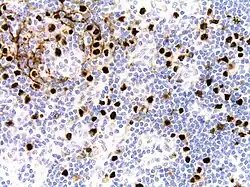

| Micrograph of HHV8-associated Castleman's Disease showing LANA-1 positive lymphoblasts in a regressed germinal center and mantle zone. LANA-1 stain. | |

Formal criteria for the diagnosis of HHV-8-associated MCD have not been published; however, diagnosis requires enlargement of lymph nodes in multiple lymph node regions (typically confirmed with radiologic imaging), histologic changes consistent with HHV-8-associated MCD on biopsy of an enlarged lymph node, and confirmation of HHV-8 infection by LANA-1 lymph node staining or peripheral blood polymerase chain reaction for HHV-8.[6] HIV testing is useful for management, but a positive result is not necessary for to diagnose HHV-8-associated MCD.[2]

Unlike the other subtypes of Castleman disease, UCD and iMCD, which can present with a spectrum of features on microscopic analysis (histology) of tissue biopsied from an enlarged lymph node, only a plasmablastic pattern of histologic features has been described in HHV-8-associated MCD. Plasmablastic features are similar to the plasmacytic features seen in iMCD and UCD, with both demonstrating increased plasma cells in interfollicular spaces. Plasmablastic features are differentiated from plasmacytic features by increased numbers of plasmablasts in follicular mantle zones.[10]

Staining with latency-associated nuclear antigen (LANA-1), a marker for HHV-8 infection, is typically positive.[11]